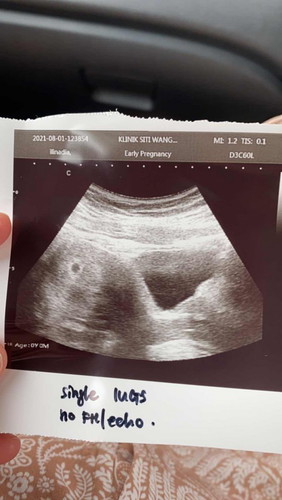

Kandungan 6 minggu

Tadi buat first scan. Ikutkn calendar baru 6weeks 5days. Tp tadi check, still kecik tak leh ukur berapa weeks. Kene tunggu lagi 2-3 minggu. Any mommies can sharee tak kandungan 6 weeks 5 days 😇 #firstbaby #bantusharing #seriusnanya